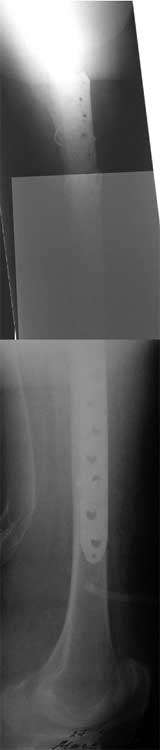

Re: Перелом бедра, через неделю после эндопротезир

послал Maxim Agalakov 07 Сентябрь 2007, 13:57

на прошлой неделе прооперировали эту пациентку, рана заживает спокойно, начала ходить с костылями без опоры на поврежденную конечность.

С уважением, Максим Агалаков